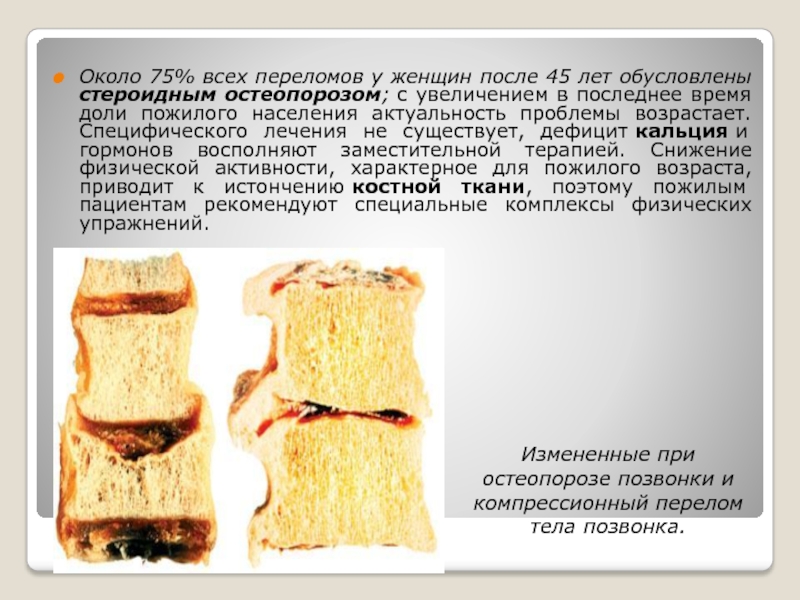

Структура грубоволокнистой костной ткани: наглядные примеры